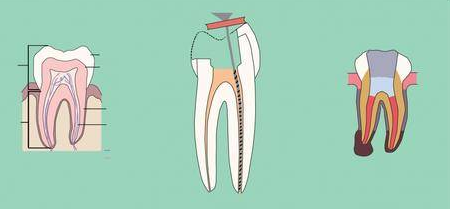

杜牙根是用於治療牙齒感染或牙髓(牙神經)受損的方法。在杜牙根過程中,牙醫會清除受感染的牙髓,清潔根管,然後填充和密封根管,以防止進一步感染。

補牙是修復牙齒上的蛀牙或損傷的方法。在補牙過程中,牙醫會清除蛀牙組織,然後填充修復材料,如樹脂,以恢復牙齒的形狀和功能。